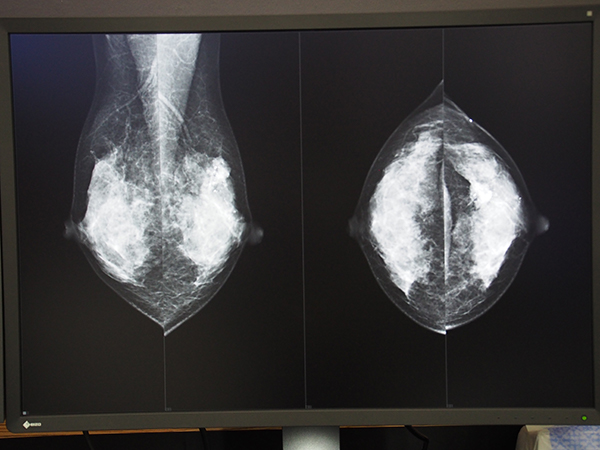

ネットカムシステムズは,ストレスのない,快適なマンモグラフィの読影環境を追究した乳腺画像診断ワークステーション「mammodite(マンモディーテ)」を出展し,実機によるデモンストレーションで,使いやすいユーザーインターフェイスと高速表示が特長のビューワ,ユーザーニーズに応える機能を実装したレポートシステムを来場者にアピールした。今回は感染防止対策として,スペースを空けて4台の端末を配置し,来場者が個別にじっくり見学できるようにした。各モニタメーカーでは,2020〜2021年にかけて12メガピクセルの製品を次々と発表しているが,mammodite はこれら最新モニタにいち早く対応している。展示ではEIZO,バルコ,JVCケンウッドの12メガピクセルモニタを使用し,来場者は快適なマンモグラフィ読影環境を体感した。

2012年に発売されたmammoditeは,すべての女性の健康,乳がんの早期発見・早期治療の実現,より正確な乳腺画像診断のサポートをめざして自社開発された,マンモグラフィ画像診断ワークステーションである。マンモグラフィの読影からレポート作成までの一連の流れをスムーズにするための,ユーザーインターフェイスと機能が実装されている。

マンモグラフィ画像は,ほかのX線画像に比べデータ容量が大きく,近年はトモシンセシスの臨床導入も進み,読影ビューワへの負荷はますます大きくなっている。そのような中においても,ストレスなく快適な読影環境を実現するため,mammoditeには独自開発の統合プロセスエンジン“APROS”を搭載し,高速な表示スピードを実現している。ここ2年ほどは,さらなる安定稼働をめざして,バックグラウンドの強化を進めている。なお,トモシンセシスにも標準対応しており,トモシンセシス画像もなめらかに表示する。また,マルチモダリティ対応のため,乳房MRIや乳腺超音波なども併用した読影も可能だ。

ユーザーインターフェイスは,マニュアルがなくても直感的に使えることをめざして開発されており,わかりやすいアイコンの配置で,次の操作にはどこを押せばいいかが直感的にわかるため,読影フローを妨げずにスピーディな操作を可能にする。オートポジショニング機能やマスキング機能,ワンタッチ過去画像比較機能により,直ちに読影を開始できるほか,腫瘤計測機能や図形オブジェクト機能など,正確な乳腺画像診断をサポートする多彩な機能を実装している。

バックグラウンド強化が進められている乳腺画像診断ワークステーション「mammodite」

使いやすいユーザーインターフェイスと高速表示が特長のビューワ